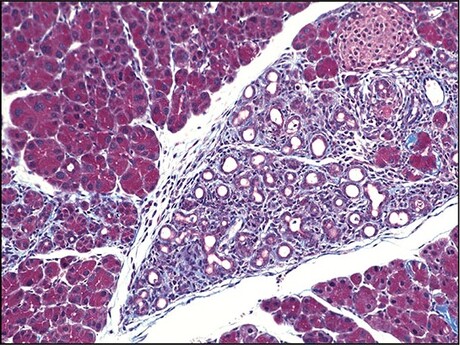

The researchers made similar findings when the mouse models were dosed with a drug called caerulein, which acts on the pancreas to force an increased output of digestive enzymes. Although animals with Fic and those without developed pancreatitis, those without this enzyme had significantly worse disease, accompanied by a significantly stronger UPR. Furthermore, although animals with Fic had a quick recovery, those without Fic developed permanent scarring in their pancreas — a sign of significantly lower resilience to stress.